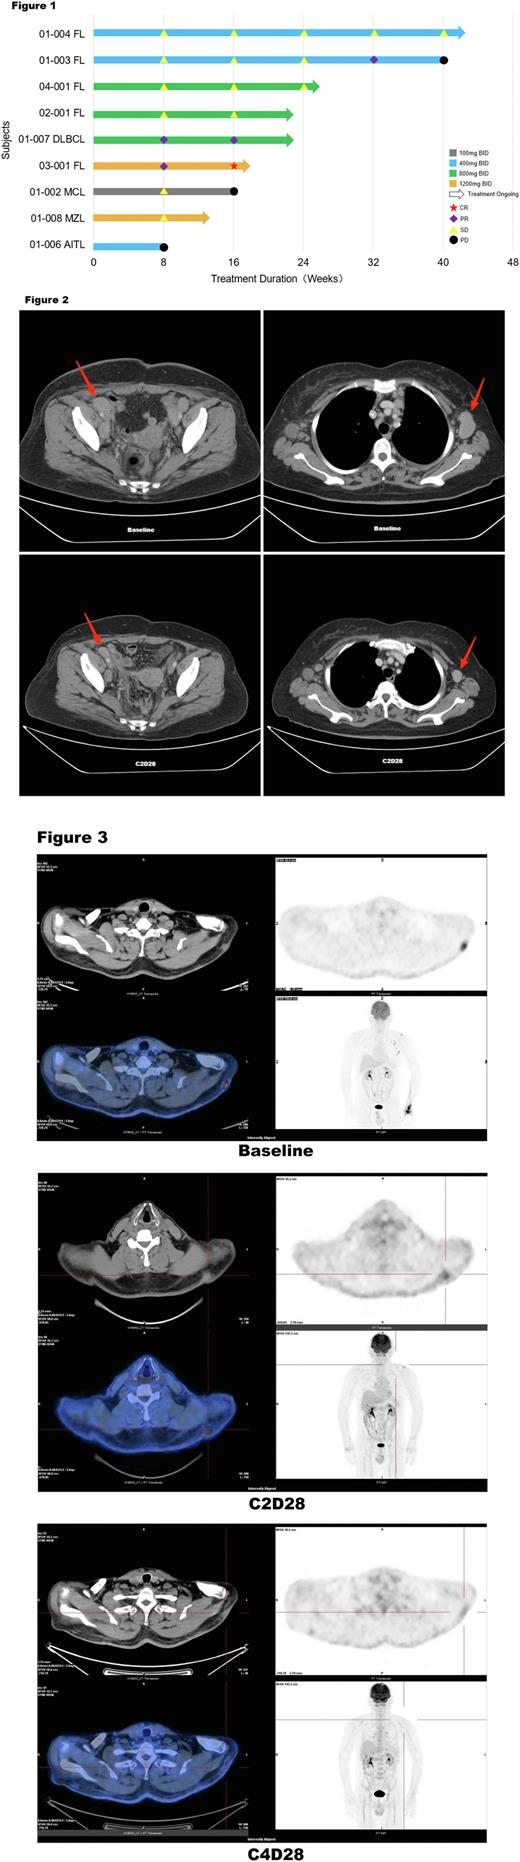

Results: In the dose-escalated phase, as July 15, 2022 , a total of 15 pts were enrolled and treated with 5 dose groups of XNW5004 (from 100 mg to 1600 mg BID). The median age was 58 years (range, 47-71). Pts received a median of 3 (range, 2-7) prior lines of treatment and diagnoses of diffuse large B-cell lymphoma (DLBCL, n = 3), follicular lymphoma (FL, n = 6), mantle cell lymphoma (MCL, n = 1), marginal zone lymphoma (MZL, n = 2), small lymphocytic lymphoma (SLL, n = 1), angioimmunoblastic T-cell lymphoma (AITL, n = 1), and Waldenström macroglobulinemia (WM, n = 1). XNW5004 had a favorable safety and tolerability, and no dose-limiting toxicity (DLT) was observed at doses up to 1600 mg BID. Grade 3 treatment-related adverse events (TRAEs) occurred in 4 (26.7%) pts, including white blood cell decreased, neutrophil count decreased, lymphocyte count decreased, and platelet count decreased. No grade ≥4 adverse events (AEs) and serious TRAEs occurred. Any grade TRAEs in ≥20% of pts included nausea (33.3%), diarrhea (33.3%), alanine aminotransferase increased (26.7%), neutrophil count decreased (26.7%), white blood cell decreased (26.7%), hypertriglyceridemia (26.7%), aspartate aminotransferase increased (20%), vomiting (20%), blood lactate dehydrogenase increased (20%), blood bilirubin increased (20%), pruritus (20%), anemia (20%). With a median follow-up of 4 (range, 2-10) cycles, the objective response rate (ORR) was 33.3%, and the disease control rate (DCR) was 78% in the 9 evaluable pts. The median progression-free-survival (mPFS) and median duration of response (mDOR) were not reached. Among pts with EZH2 wild-type (WT) FL (n=5) , the ORR was 40%, the DCR was 100%, the mPFS and mDOR were not reached. In all pts with stable disease (SD), the lesions continued to shrink. One patient (Figure 2) with DLBCL (non-GCB) received 2 cycles of XNW5004, the lesions were reduced by 59.8%; and after 4 cycles of treatment, the lesions were reduced by more than 70%. One patient (Figure 3) with FL (EZH2 WT) received 2 cycles of XNW5004, the subcutaneous lesions and axillary lymph nodes were significantly reduced, PET-CT showed that uptake was strongly reduced, and the Deauville score (DS) was 5 and 3, respectively. The efficacy evaluation was partial response (PR). After 4 cycles of treatment , PET-CT showed that the metabolism of subcutaneous lesions and axillary lymph nodes continued to decrease, the DS was 2 and 1, respectively, and the efficacy evaluation was complete response (CR). In addition, the PK of XNW5004 was well.